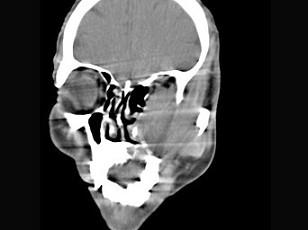

男,65岁,左眼球突出近一年,鼻涕带血,面颊部隆起,同时面颊部有麻木感,CT检查如图,最可能诊断为 ( )